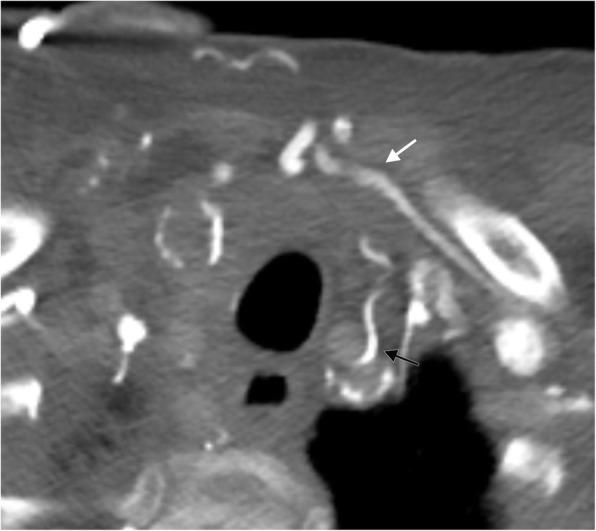

In the healthy patient, blood returns to the heart via classic venous pathways. Obstruction of any one of these pathways will result in blood flow finding new collateral pathways to return to the heart. Although significant anatomic variation exists and multiple collateral vessels are often present in the same patient, it is a general rule that the collateral pathways formed are a function of the site of venous blockage. Therefore, knowledge of typical collateral vessel systems can provide insight in localizing venous obstruction and characterizing its severity and chronicity. In addition, knowledge of collateral anatomy can be essential in interventional procedural and/or surgical planning, especially when placing catheters in patients with venous blockage. In this pictorial review, we provide a systematic approach to understanding collateral pathways in patients with venous obstruction in the upper body.

在健康患者中,血液通过经典静脉途径回流至心脏。这些途径中任何一条受阻都会导致血流寻找新的侧支途径回流至心脏。尽管存在显著的解剖变异,且同一患者体内常存在多条侧支血管,但一般规律是,形成的侧支途径取决于静脉阻塞的部位。因此,了解典型的侧支血管系统有助于定位静脉阻塞并判断其严重程度和慢性化情况。此外,了解侧支解剖结构对于介入操作和/或手术规划至关重要,尤其是在为静脉阻塞患者放置导管时。在本图文综述中,我们提供了一种系统方法,用于理解上身静脉阻塞患者的侧支途径。